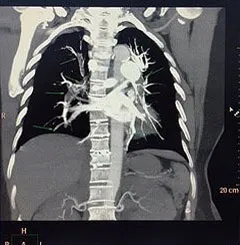

Qua các kết quả cận lâm sàng cấp cứu của bệnh nhân cho thấy huyết khối lấp hoàn toàn động mạch phổi phải, động mạch phổi trái ở đoạn gốc và các phân nhánh. Siêu âm tĩnh mạch chi dưới thấy huyết khối lấp hoàn toàn tĩnh mạch đùi nông, tĩnh mạch khoeo, chày trước và chày sau chân phải.

Huyết khối lấp gần hoàn toàn các nhánh động mạch phổi hai bên, trong nhĩ phải và Tĩnh mạch chủ dưới lan xuống tận các tĩnh mạch trên gan